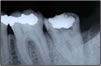

【再生治療】

歯周病などで骨などを失ったところに骨を再生させたりします。

再生治療前再生治療後

▲治療前▲治療後